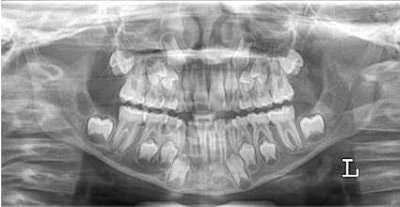

More recently, a group from the Katholieke Universiteit in Leuven, Belgium, tested Kvaal's dental age calculation technique on panoramic dental radiographs. Dr. Nathalie Bosmans and colleagues gathered 197 digital orthopantomographs from three Belgian dental practices. The subjects were all Caucasian (95 females, 102 males) with a mean age of 34.7 years.

Six teeth were selected for analysis per Kvaal's method:

- Maxillary central

- Lateral incisors

- Second bicuspids

- Mandibular lateral incisors

- Canines

- First bicuspids

For all six teeth, Bosmans' group measured the maximum tooth length, the pulp length, the root length on the mesial surface from the enamel-cementum junction (ECJ) to the root apex, the root and pulp width at the ECJ level, the midroot level, and the midpoint between the ECJ and the midroot level. Software that automatically calculates dental age was used to analyze the data. Months later a single observer evaluated the x-rays.

| "Morphologic assessment is great in dead individuals. In living people, you only have the radiology option," co-author Dr. Guy Willems said. The observer in this study had no idea as to the chronological age of the individuals whose panoramic x-rays were used. |

"Statistical analysis was carried out in order to spot significant differences between the chronological age and the calculated age," the authors explained (Forensic Science International, October 29, 2005, Vol. 153:2-3, pp. 208-212).

The results showed a high concordance correlation between the calculated dental age and the chronological age when measurements from all six teeth were used or when only three mandibular teeth were used. However, using any other combination of teeth resulted in significant differences the between calculated age and the real age.

The authors concluded that their high degree of intraobserver agreement indicated the high reproducibility of using Kvaal calculation on panoramic x-ray.